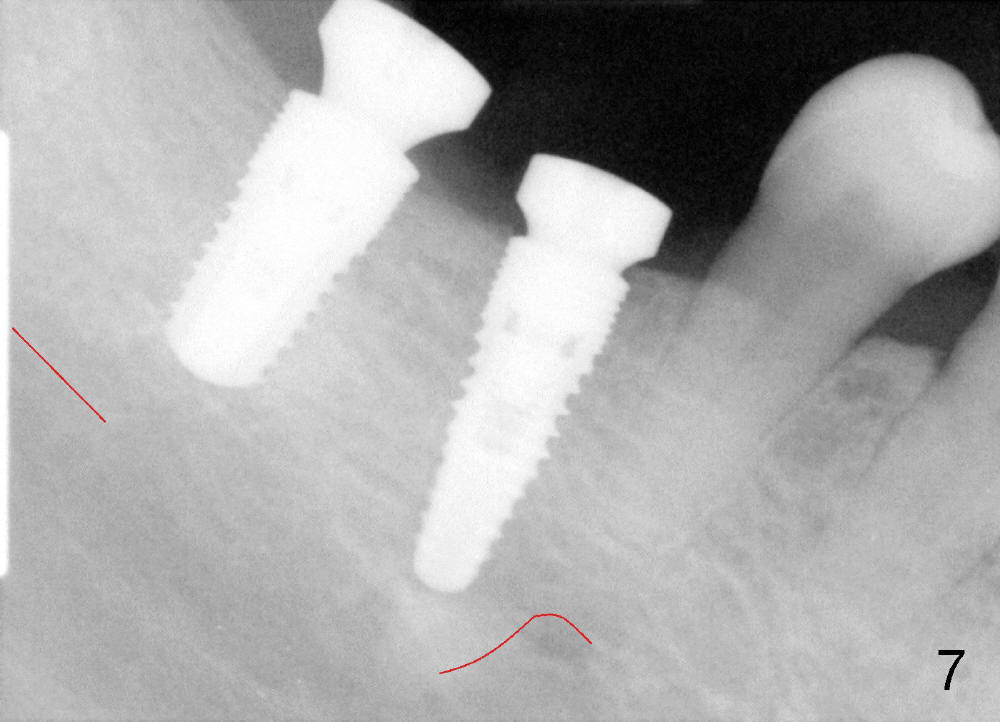

Finally 5.3x10 mm SM implant is placed at #31 (Fig.7). Healing abutments (Ɵ5.2x3(1) and 6.2x4(2) mm) are placed at #30 and 31, respectively (Fig.7-9).